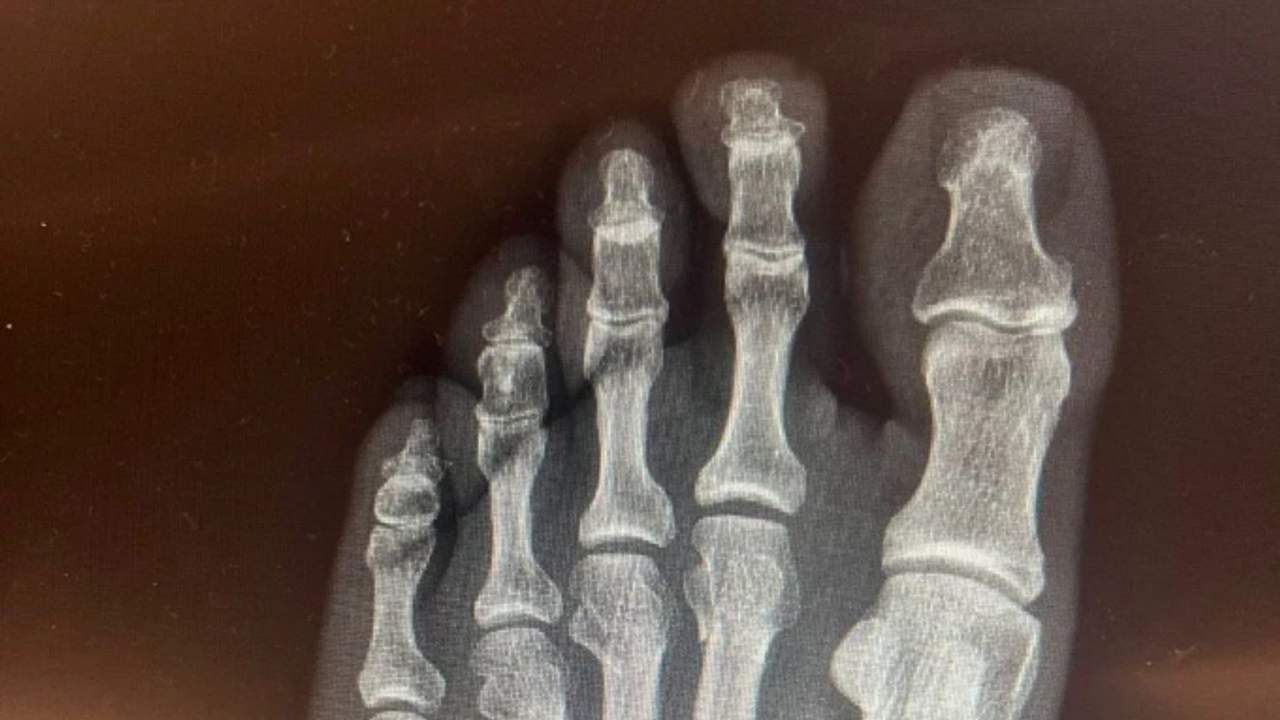

He published an X-ray of his foot to end the controversy

Özgür Özel's broken foot caused controversy at the time, and he stated that his foot was broken in an accident at home. In response to this, some allegations were made on social media claiming that his foot was not broken at home, but as a result of the chaos during an argument, and even that he had been shot. Özel denied these allegations and shared an X-ray of his broken foot.